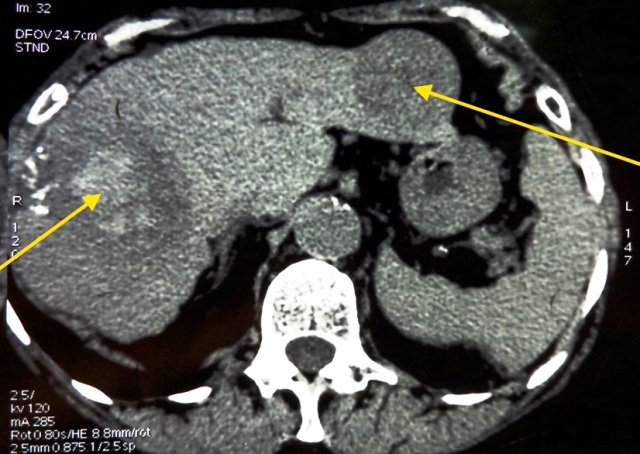

Первичным методом инструментальной диагностики рака печени в большинстве случаев служит УЗИ органов брюшной полости (печени). УЗ-сканирование позволяет выявить очаговые поражения печени, предположить их характер (первичный, метастатический), определить размеры. В ряде случаев УЗИ используется для проведения прицельной чрескожной биопсии печени и установления морфологического диагноза. Уточнение полученных при эхографии сведений производится с помощью КТ или ЯМРТ.